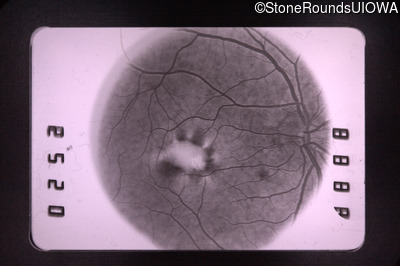

Fluorescein Angiography - Left - 20/30 -3

Exemplar